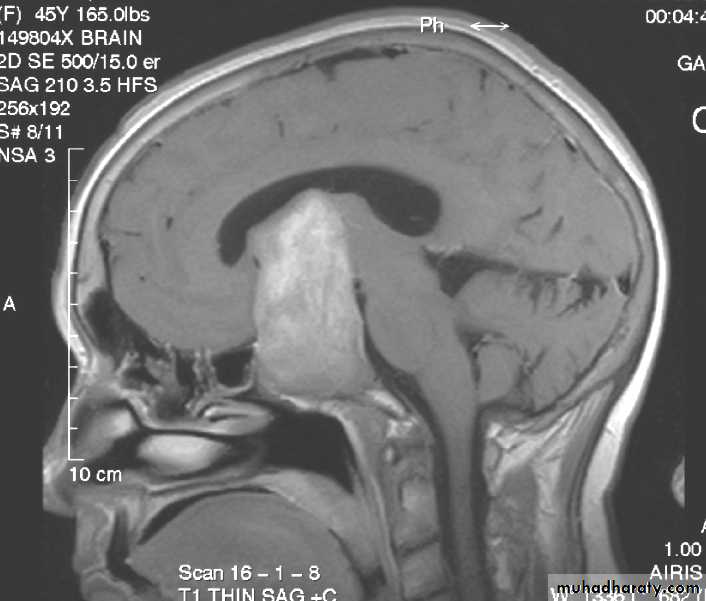

Pituitary Tumours

• Their presentation is by optic chiasm compression that cause visual field defect (bitemporal hemianopia).

• The usual treatment is microscopic trans-sphenoidal or trans-cranial excision.

Functioning pituitary adenomas

• 2. Adenomas may be further divided according to their sizes into Microadenomas that are less than 1 cm in diameter, and Macroadenomas that have a larger size.

• 3. Functioning adenomas are diagnosed by:

• Radiology by using MRI and CT scan.